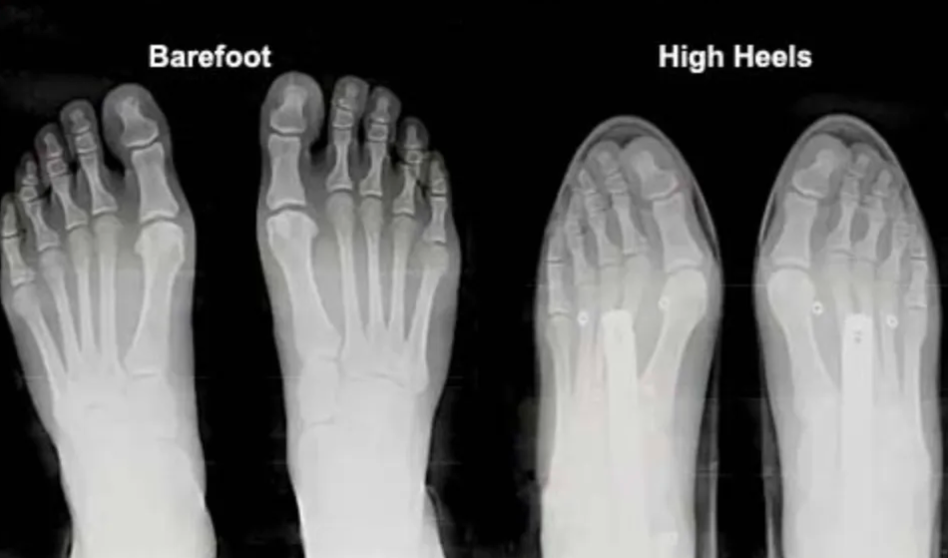

Modern people are increasingly disconnected from barefoot experiences. The invention of high heels, running shoes, sandals, and slippers has almost eliminated opportunities for barefoot walking. However, most footwear hasn't solved many problems; instead, certain shoe designs have introduced new injuries like bunions from pointed heels and flat feet from soft, thick-soled shoes. Unnatural footwear designs often weaken the natural functions of our feet.

Strengthened Foot Muscles and Arch Function

A study from the University of Liverpool demonstrated that highly structured, supportive shoes restrict sensory input and gait control, leading to decreased foot strength and impaired mobility over time. The research compared barefoot, minimalist footwear, and conventional shoes, finding significantly greater sagittal and frontal plane stability with barefoot and minimalist conditions.